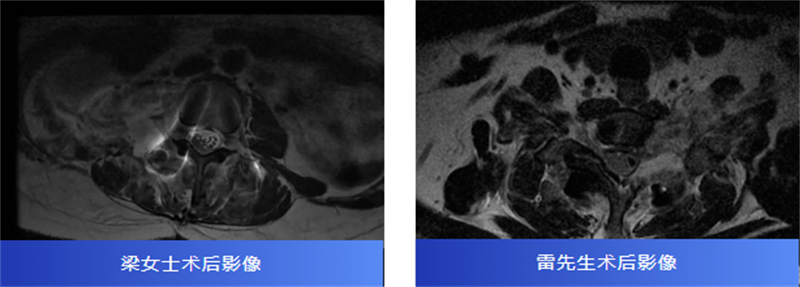

后来,经过腰椎磁共振检查,才发现原来是椎管内长了一个肿瘤,压迫着神经,并向外生长,延伸到了右肾附近,情况十分复杂。

两名患者转诊至柳州市人民医院后,脊柱外科主任、主任医师胡巍博士迅速组织医学影像科、麻醉科等多学科会诊。团队对肿瘤病变范围、与神经的毗邻关系进行周密评估,为每位患者制定个体化手术方案。

术中,在显微镜辅助下,医生精细分离肿瘤与神经组织,小心翼翼解除压迫,最终切除了肿瘤。病理报告也带来好消息:两人均为良性神经鞘瘤。

术后,梁女士的腰腿痛消失了,雷先生的颈肩胀痛也得到了缓解。两位患者都保住了正常的神经功能,步入康复的新阶段。